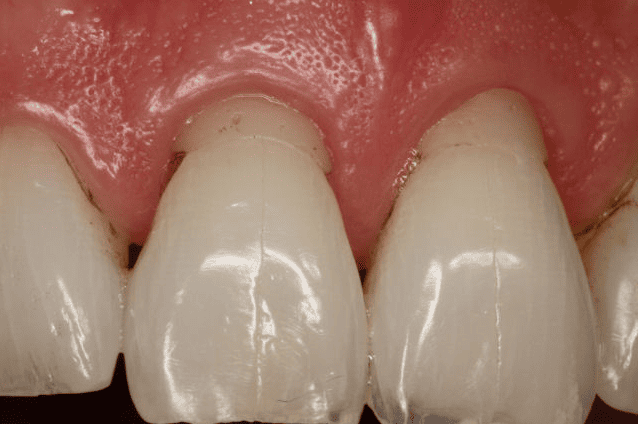

After

Patient: Jill